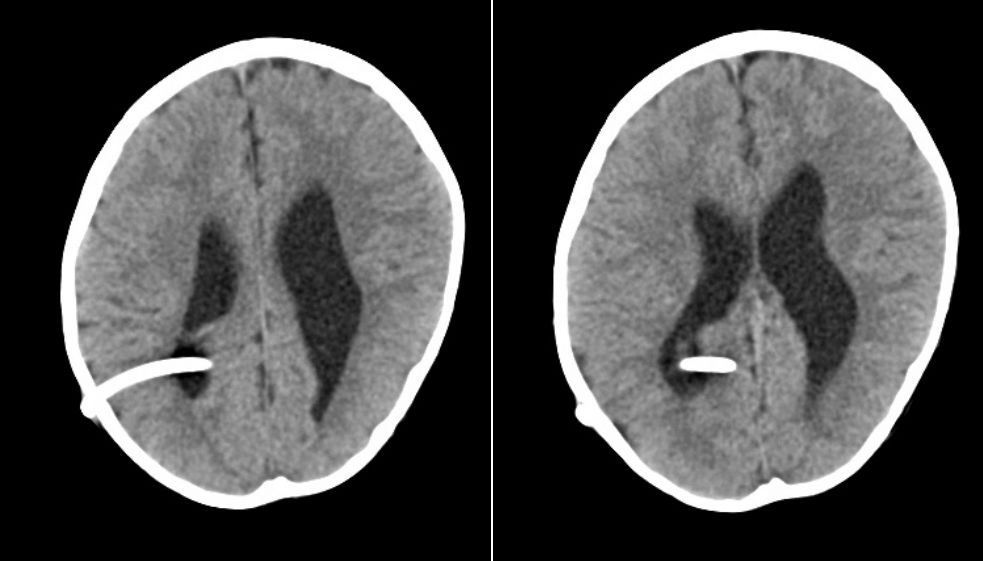

病例1,头颅CT及MRI检查提示:幕上脑室扩张,皮层菲薄,第四脑室形态正常。梗阻性脑积水,导水管部位梗阻可能。(图1)。

图1.头颅CT及MRI检查提示:幕上脑室扩张,皮层菲薄,第四脑室形态正常。梗阻性脑积水,导水管部位梗阻可能。

病例2,头颅CT及MRI检查,结果与病例1类似。